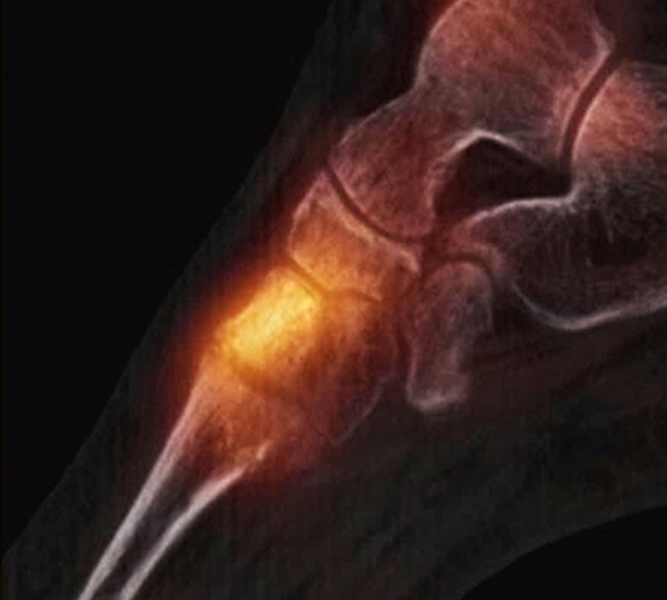

Abbildung 2.1.

Bildbeispiele symptomatische OCL

Zum Lesen der Bildbeschreibung und zur Vollansicht bitte das Bild anklicken. Bild: H. C. Rischke